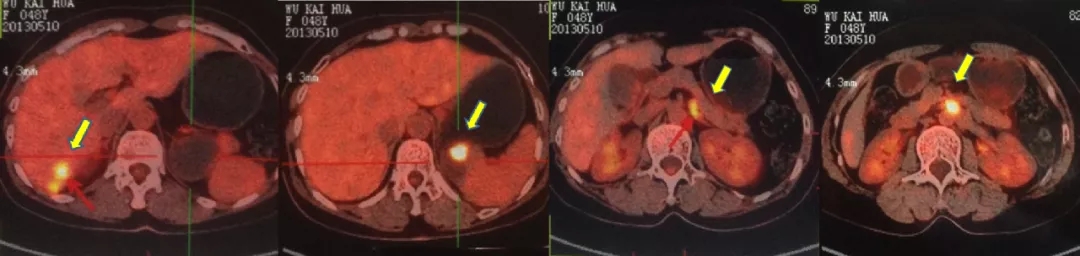

2021.5.8 PET-CT:肝肾隐窝转移灶。2021.5.12复查CA125水平为95.5U/ml。

PET-CT检查结果